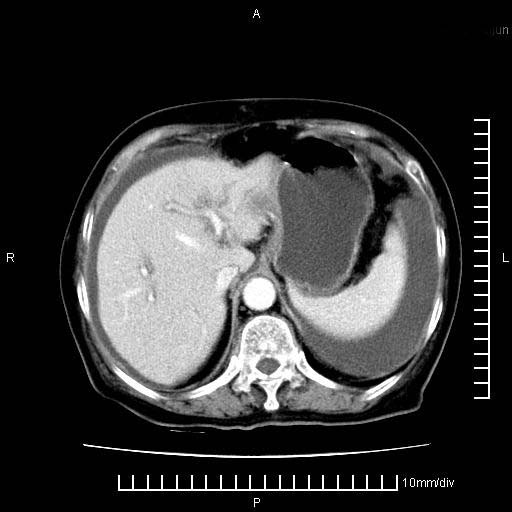

上腹疼痛月余,外院核磁诊断胰腺癌。现临床示右下腹可明显触及包块,可片子上怎么没有看到?

1.胰腺颈体部癌。

2。腹腔积液。

4。右肾盂囊肿。

胰腺体部癌累及周围器官,腹膜、粘连

1。胰腺ca伴腹膜腔转移

2。肝左叶低密度灶,考虑转移可能

胰腺体部癌累及周围器官,腹膜、粘连,临床摸到的可能是粘的组织

支持胰腺癌肝内转移,腹水改变。

胰腺结构模糊,胰尾部见囊性包块,周围脂肪密度增高,左肾前筋膜增厚,胸水、腹水。不符合胰腺ca伴腹膜腔转移。考虑胰腺炎伴假性囊肿形成、胸腹腔积液。

右肾盂囊肿。

1、考虑胰腺癌伴腹膜腔转移,胸腹水。

2、肝脏转移可能。

3、右肾盂囊肿。

1)考虑胰腺癌并胰腺假性囊肿形成。2)肝内低密度灶,不排除转移。3)右肾盂积水。4)腹水。5)右侧胸腔积液并右肺下叶部分膨胀不全。

考虑胰腺ca伴腹膜腔转移、肝左叶转移、右肾积水。右胸腔积液。